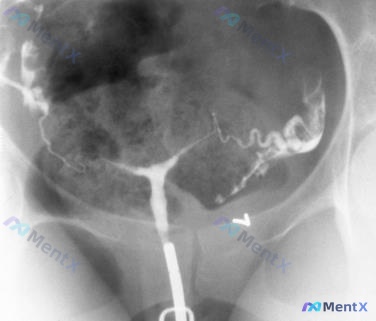

子宫输卵管造影术(HSG)是我们常用的输卵管通畅性检查,但临床中到底哪些情况能做、哪些不能做?操作有哪些必须遵守的规范?我整理了《输卵管性不孕全流程管理中国专家共识(2023年版)》和《输卵管通畅性检查专家共识》两份文件的明确要求,把核心合规标准梳理出来,大家看看有没有遗漏的点。 明确适应症 符合以...